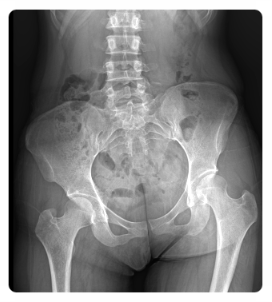

또 골반의 좌우 틀어짐은 허리에 직접적인 영향을 줍니다.

골반이 한쪽으로 돌아가면 척추가 비틀리고, 한쪽 디스크에 과도한 압력이 집중되죠.

이 상태가 지속되면 디스크 퇴행이 빨라지고 통증이 심화됩니다.